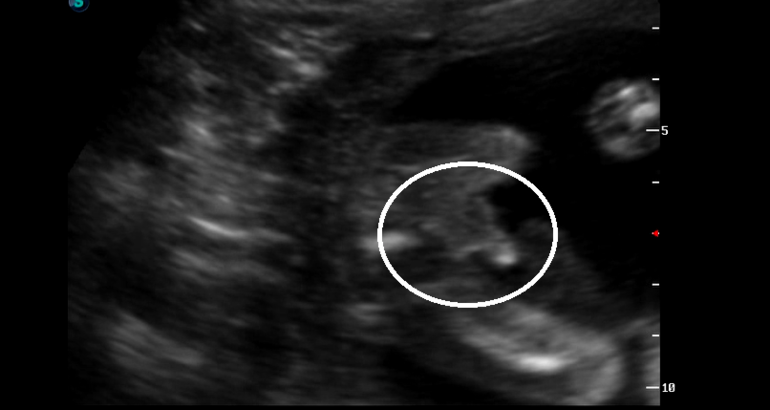

ну и несколько фото:

наши сладкие пяточки:)